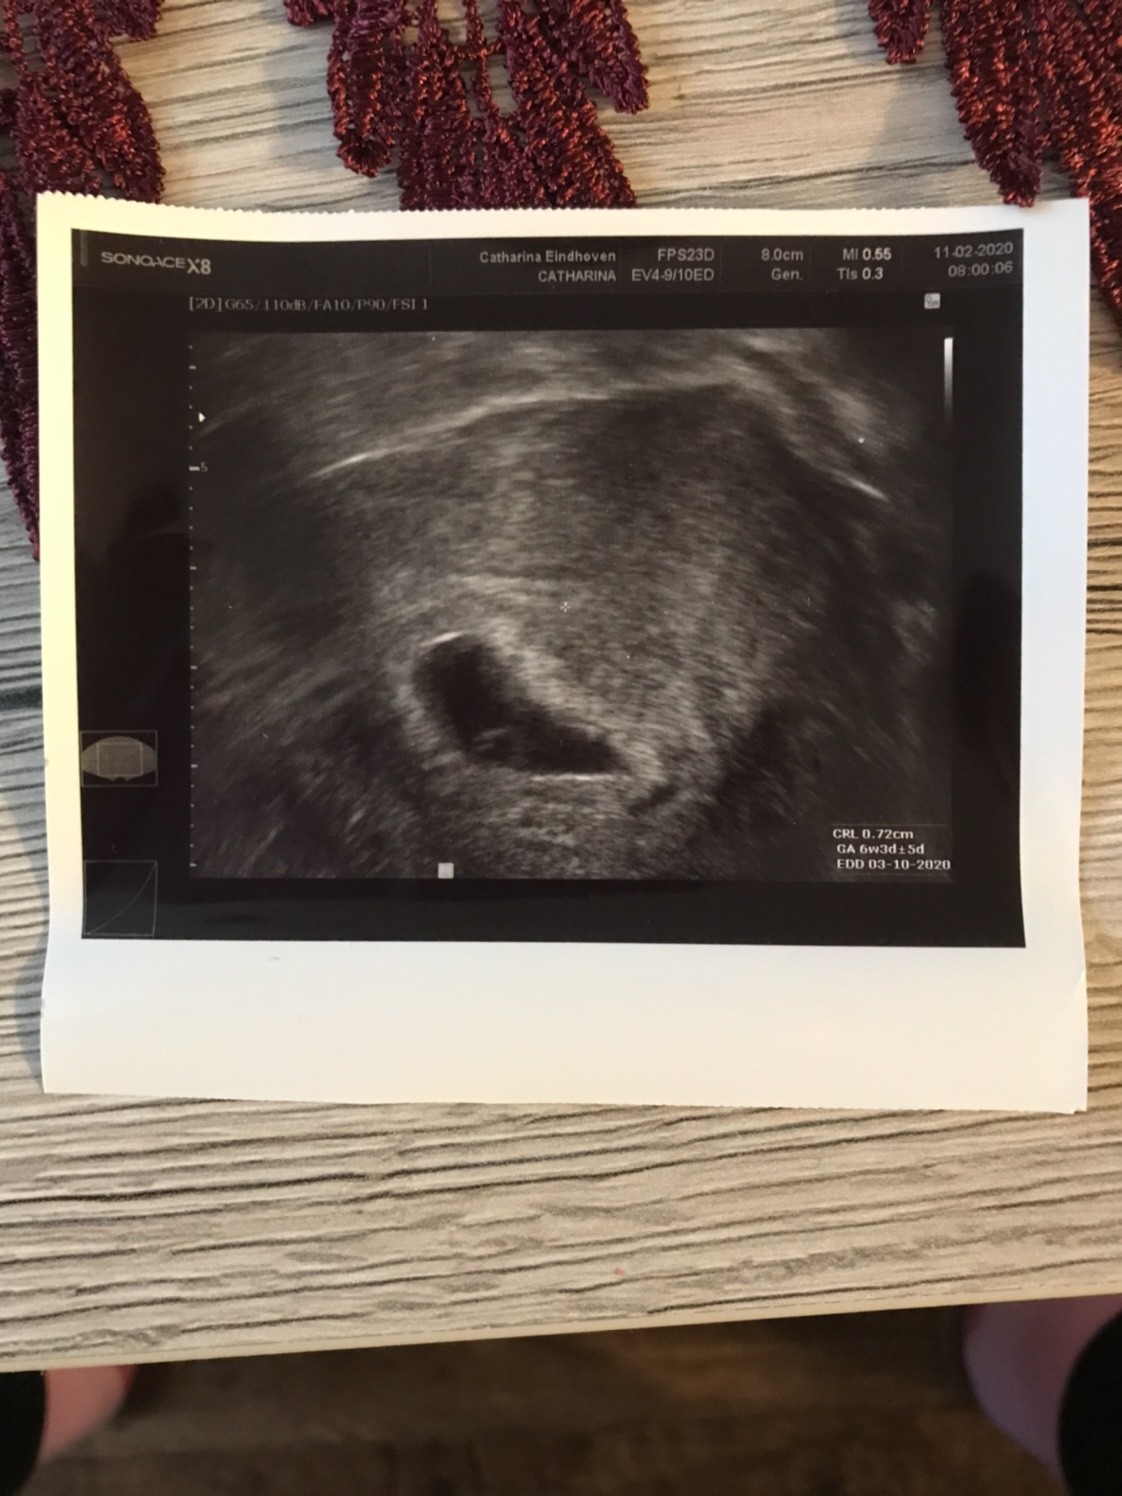

Moje zdjęcie z usg dla przypomnienia

Moje, 6t1d